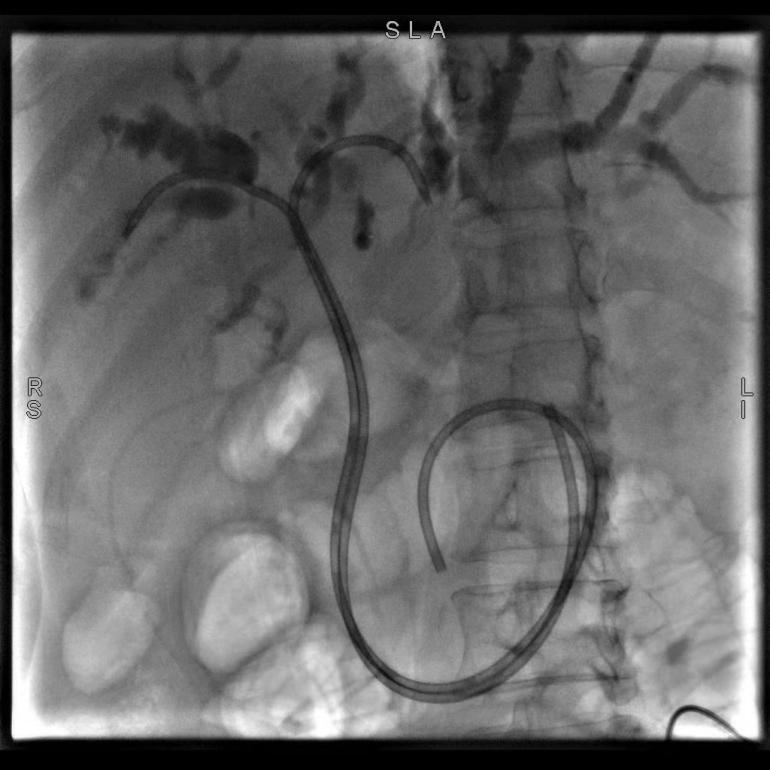

56歲的患者巫某,因“確診結(jié)腸癌伴肝轉(zhuǎn)移3年,皮膚鞏膜黃染1周”入院,完善檢查后,診斷為梗阻性黃疸、肝繼發(fā)惡性腫瘤。陶銳主任醫(yī)師組織團(tuán)隊(duì)在討論了巫女士的病情后,決定實(shí)施ERCP+EST+ERBD術(shù),術(shù)中主刀陶銳主任醫(yī)師根據(jù)患者的病情置入了鼻膽管改良塑料支架,患者術(shù)后引流通暢,梗阻情況明顯好轉(zhuǎn)。

(圖示為置入鼻膽管改良塑料支架)